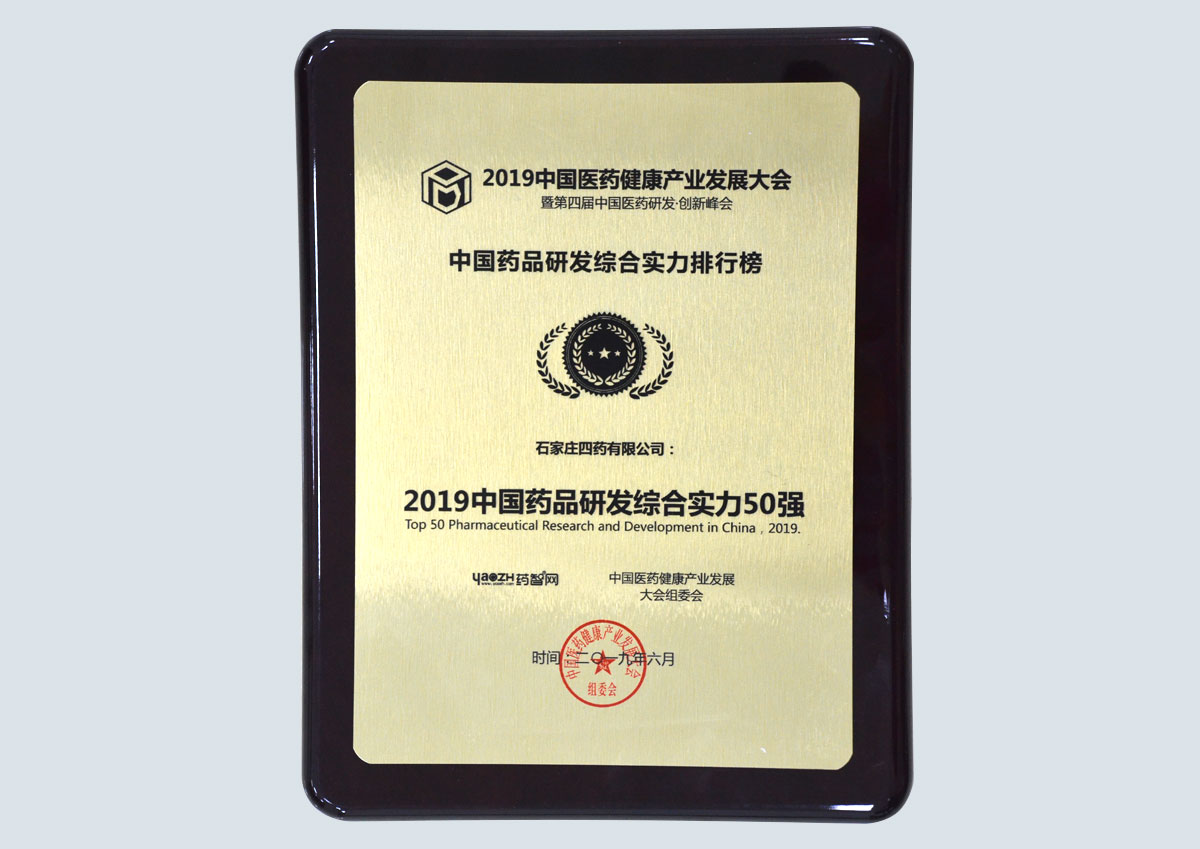

专利证书